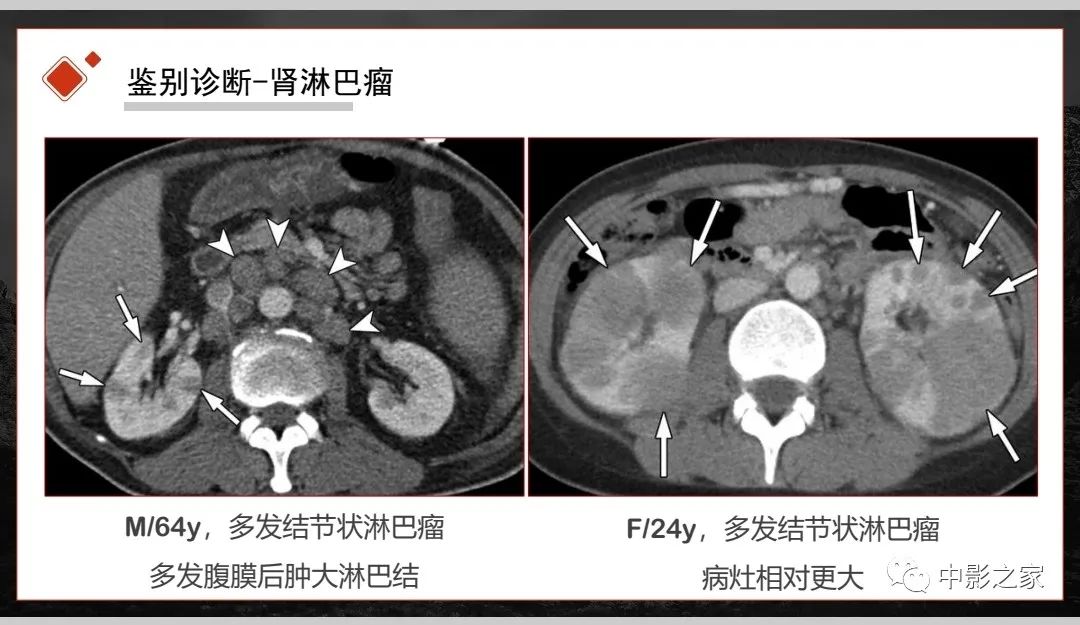

肾脏IgG4-RD临床、病理及影像特征